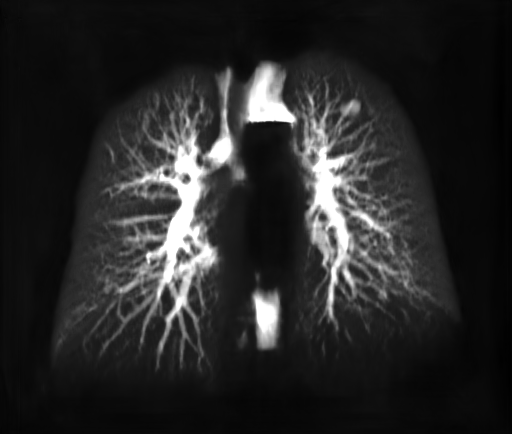

A DRR can now be generated as before for GLungsubscript𝐺𝐿𝑢𝑛𝑔G_{Lung} using Eq.3. As a consequence, the DRR generation process is now limited to the lung area. An example result of the “Lung X-ray” generation process is given in Fig.4. It is noticeable that only inner lung structures appear, excluding overlapping anatomical structures.

Refer to caption

(a)

(b)

Figure 4: (a) DRR Source Image: (b) “Lung X-ray” Target Image for Training